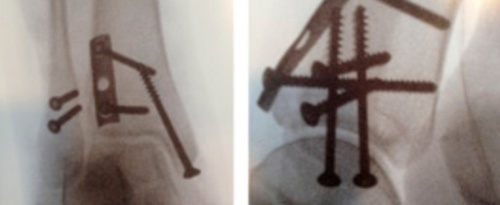

原因:全身最大的跗骨,跟骨的压缩骨折(图 5)并不常见,其发生率仅位于跖骨之后。好发于运动员,军人,以及骨质疏松的老年人。多由于反复的负荷过重以及骨吸收与成骨不一致引起。

跟骨压缩骨折: 跟骨侧位片箭头所示

临床表现:疼痛多剧烈,弥散沿着跟骨内外侧分布。活动及负重时加重,休息时也不见得减轻。沿跟骨外侧有压痛,跟骨挤压实验阳性。

诊断:跟骨侧位片在症状产生 2-8 周后可以显示跟骨骨小梁的破坏,尽管这些图片在疾病的早期多被认为正常。与正常骨小梁垂直的硬化骨线预示着压缩骨折的愈合。当疼痛持续而平片没有证据时,MRI 或者骨扫描有助地诊断。

治疗:包含积极的处理,短腿石膏固定 4-8 周。还包括补充 VD 以及进行骨密度检测。经过固定后,正常活动可以恢复。预后是良好的,极少需要手术。严重的错位与力线异常不常见,不愈合的可能低。